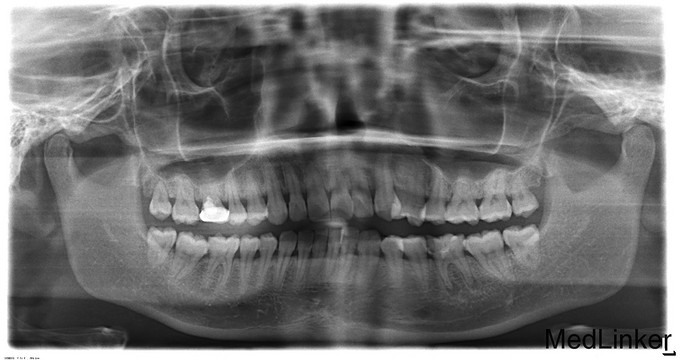

36颌面深大龋洞,冷测无反应,叩痛(++),无松动,根尖部扪诊疼痛

36慢性根尖周炎